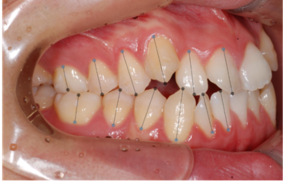

이미지/라벨링 예시

| 이미지 | 라벨링 | |

|---|---|---|

| front |

치아경계/치축